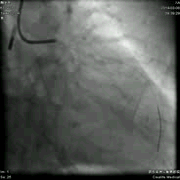

左冠造影:左主干末端偏心性、钙化狭窄,程度95%。 前降支开口狭窄80%,中段弥漫性叉口病变,狭窄85%,远段血管纤细,TIMI血流2级。中间支起始部局限性扩张。 回旋支开口狭窄70%,近中段弥漫性叉口病变,狭窄85%。

右冠造影: 右冠中段弥漫性狭窄,程度70%,PL远段狭窄90%。可见向左冠脉提供侧支循环。

造影结论及应对: 本例患者发生急性心肌梗死时间不详,未行急诊PCI术。入院后已有心功能不全表现。行冠脉造影发现:左主干末端狭窄严重,为四分叉病变,前降支远段血管纤细,血流不佳。回旋支偏细,病变弥漫。右冠脉优势型,中段弥漫性狭窄。SYNTAX积分31分,为中度积分,可选择CABG,PCI依然是合理选项。根据患者个体特征及患者意愿,最终决定采取介入治疗,为增加手术安全性及降低风险,术前植入IABP,并详细交代手术风险及获益。